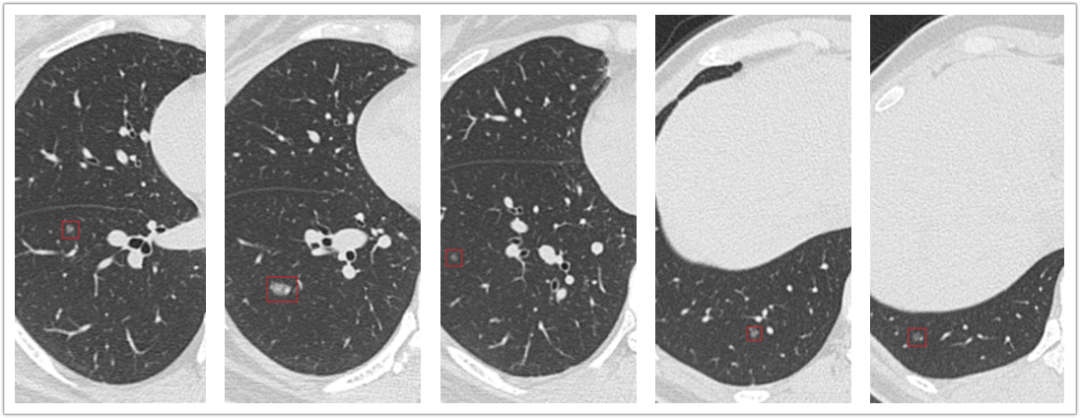

致力于肺结节诊治。

肺癌、食管癌等胸部恶性肿瘤的综合外科治疗,在重症胸部外伤及疑难疾病治疗方面有丰富经验。

开展微创胸腔镜手术,在肺大疱、漏斗胸、手汗症等手术疗效满意,对微创胸腔镜下肺癌、食管癌、纵膈肿瘤的手术治疗取得良好的效果。